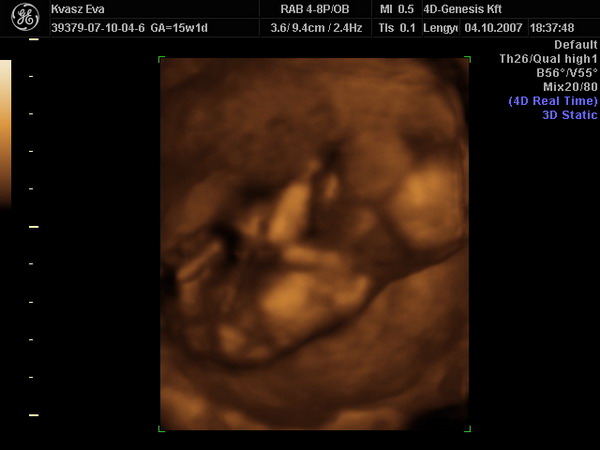

Megérkeztünk a 4D-ről.

Hát, ennyit a megérzéseimről. :cry: A gyermek egyértelműen megmutatta, hogy márpedig ő nem lesz Zsófi. Apa majd kiugrott a bőréből. Ezek szerint ő is fiúpárti. :roll: Mostantól én sem panaszkodhatom arra, hogy nincs bennem fütykös. :lol: :lol: :lol: :lol: :lol:

Mindjárt próbálok képet is feltenni, mert az összeset megkaptuk cd-n.

LEXA!!!!! Ha előkerültél írd be a táblázatba légyszíves, hogy Botondunk lesz. :lol:

Az első képen jól nézzétek meg a lábam közét!!! :lol: :lol: :lol: :lol: :lol: :lol: :lol:

Irigyellek, h ilyen mázlitok volt, h ilyen szép képeket sikerült készíteni. Ez azért ritka ilyen fiatal terhességnél..

Az első uh kép, olyan mint egy Leonardo rajz.

Gyönyörű ez a gyerek. Gratula hozzá!!! :lol:

Évi! Annyira gyönyörű az a 4D-s kép! Nagyon tetszik! Már én is alig várom, hogy menjünk. Neked hol csinálták? Gyűjtöm az infókat, hova érdemes menni, mert ami nekünk legközelebb lenne ( a szegedi) azt nagyon nem ajánlották...

Xien, mi Bp- voltunk a 4D Genesisben, de gondolom az neked kissé messze van. Bár, ha jössz a talira... :wink: